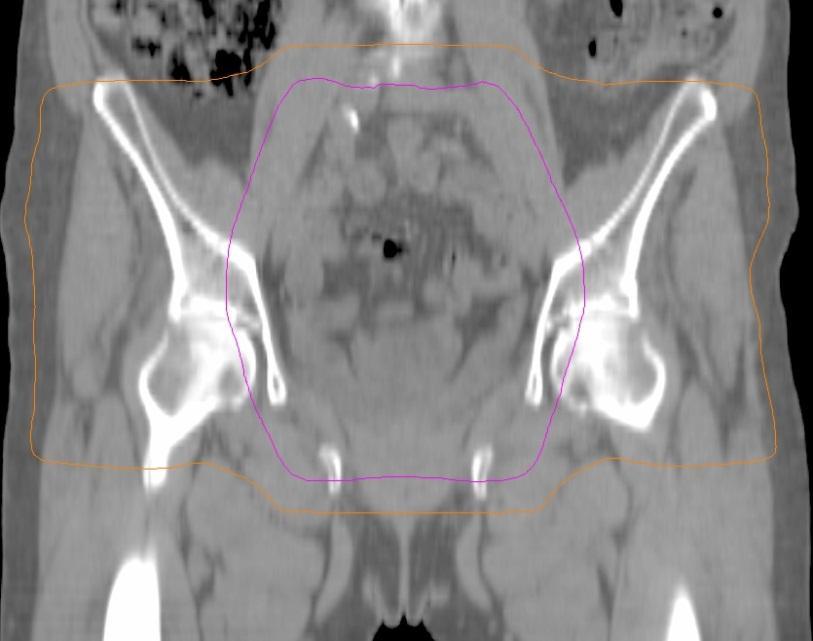

External Beam Radiotherapy

•Treats vaginal cuff, parametrium, pelvic lymph nodes

•Daily treatment (M-F) for 5 weeks

•High risk patients

• External beam RT

• Total dose: 45-50 Gy

• ~2 Gy daily

• 25 treatments over 5 weeks

Simulation

• CT scan

• Immobilization device

• Draw tumor and normal structures on CT slice-by-slice (“contouring”)

• Entire treatment based on this CT scan